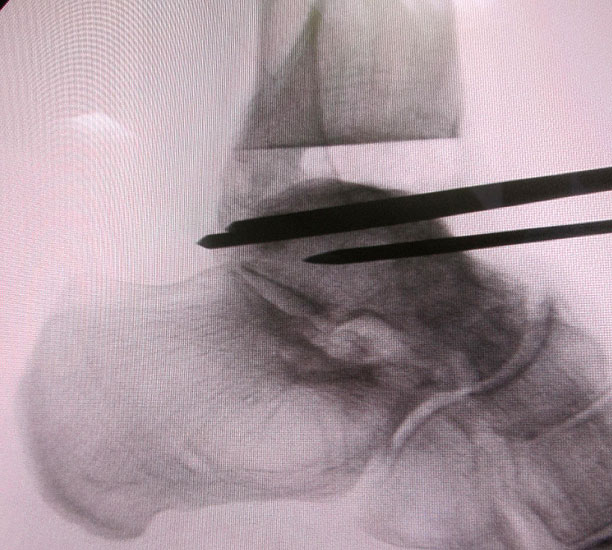

Osteosynthese eines intraoperativ frakturierten medialen Malleolus mit perkutanen Schrauben.

Abbildung 19

1. intraoperative Innenknöchelfraktur:

Mögliche Ursachen können eine zu weit medial plazierte Tibiakomponente oder eine zu weit mediale, nicht nach lateral konvergierende Sägerichtung im Rahmen der ventrodorsalen distalen Tibiaresektion sein (Abb. 19).